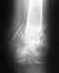

По заключениям к анализам(КТ, МРТ, Рентген) пишут артроз , кэм-импиджмент, киста левого тбс.Скажите пожалуйста, что возможно сделать в данной ситуации чтобы избежать ендопротезирования тбс и остаться физически активным.

КТ:

МРТ и Рентген:

• Кликните для загрузки файла 1.jpg